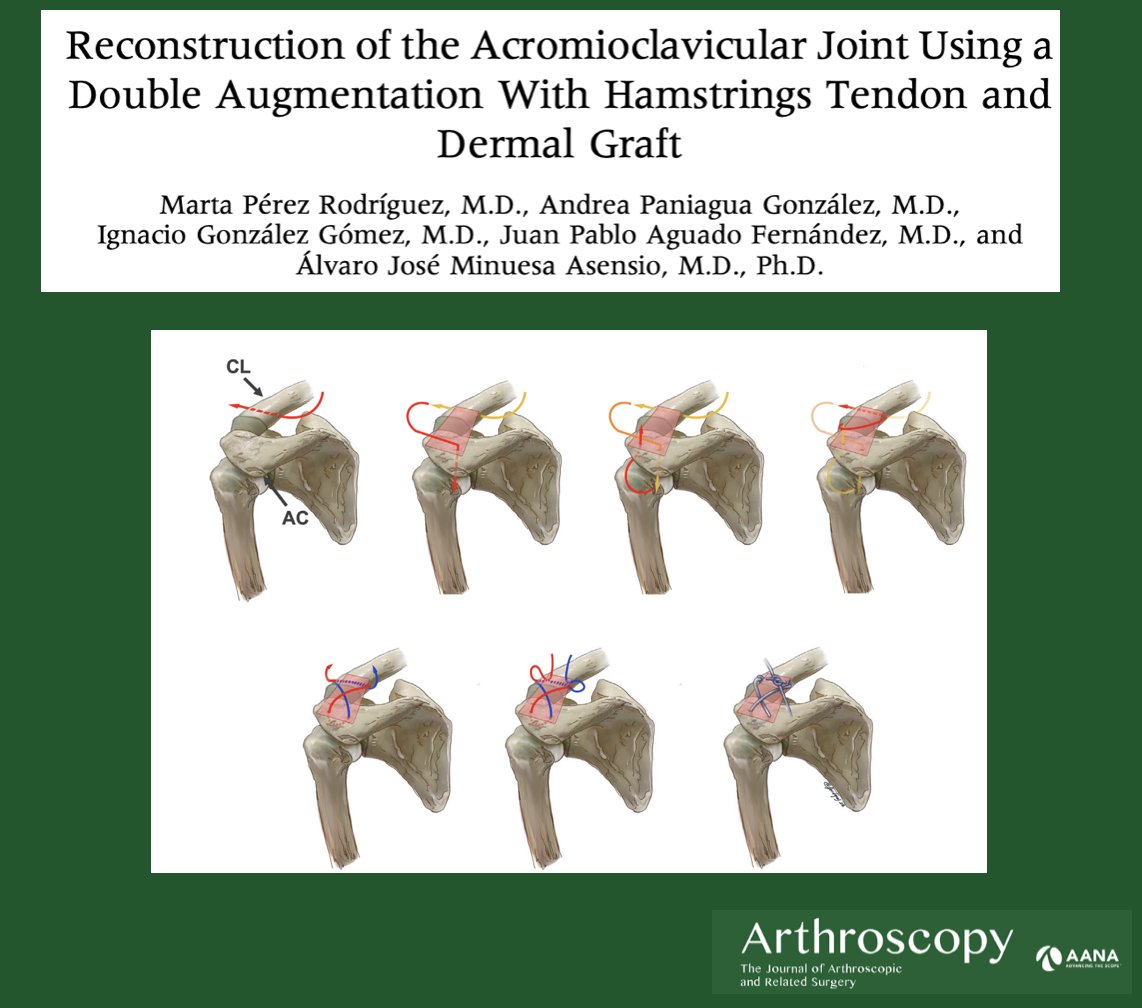

Brian Waterman, MD with his commentary on the clinical usefulness of classic anterolateral acromioplasty vs. lateral acromioplasty in cases of RTC tears with an increased critical shoulder angle. ow.ly/MS6550LGcgt